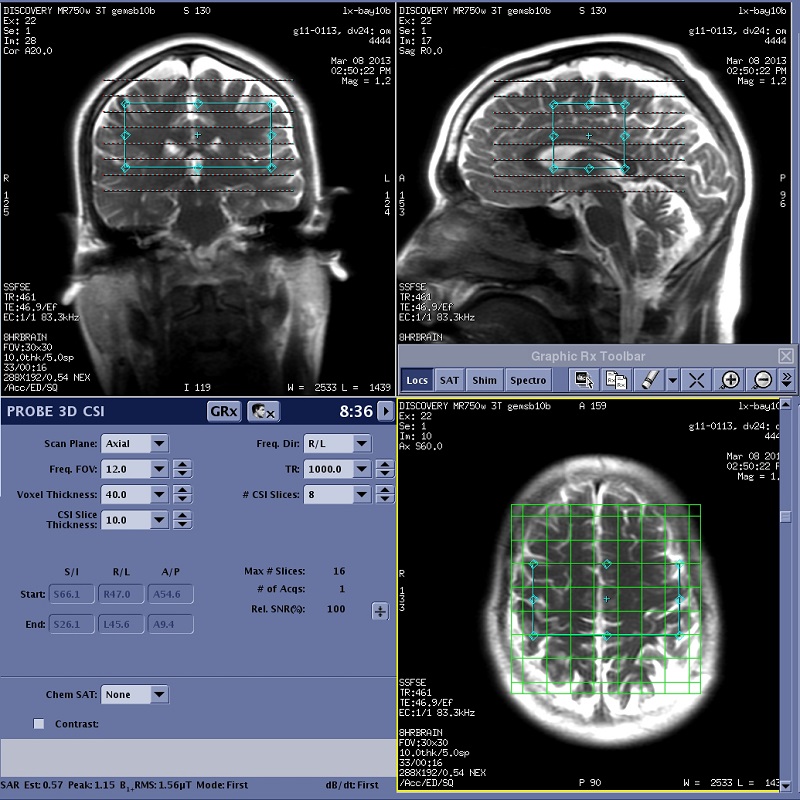

PROBE 3D CSI: acquire a scan

In order to display the localizer image in READY View, the center of each reference slice must be within 0.8 mm of each CSI slice. If a slice that meets this criterion does not exist in the selected reference series, READY View displays an error message, "Localizer loading failed, no matching image". Click OK to the error message. READY View launches, but an image does not display in the lower-left viewport. To avoid this problem, follow these guidelines when prescribing a 3D CSI scan.

Important: Do not save the 3D CSI protocol as an oblique plane. Save the protocol as an axial plane and then change the plane to oblique when you are viewing/editing the series.